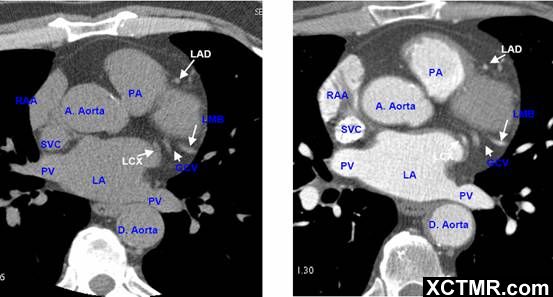

常用英文名称及缩写 LA - Left Atrium 左心房 RA - Right Atrium 右心房 LV - Left Ventricle 左心室 RV - Right Ventricle 右心室 Mitral Valve 二尖瓣 A. Aorta-Ascending Aorta 升主动脉 D. Aorta-Descending Aorta 降主动脉 SVC – Superior Vena Cava 上腔静脉 IVC – Inferior Vena Cava 下腔静脉 PA - Pulmonary Artery 肺动脉 PV - Pulmonary Vein 肺静脉 LMA - Left Main Artery 冠状动脉左主干 LAD - Left Anterior Descending Artery 左前降支 LCX - Left Circumflex Artery 左回旋支 LMB - Left Obtuse Marginal Branch 左边缘支(钝缘支) RCA - Right Coronary Artery 右冠状动脉 PDA - Posterior Descending Artery 后降支 Conus Branch 右动脉圆锥支 LAA – Left Atrial Appendage 左心耳 RAA – Right Atrial Appendage 右心耳 CS - Coronary Sinus 冠状窦 MCV – Middle Cardiac Vein 心中静脉 GCV –Great Cardiac Vein 心大静脉 PIVV – Posterior Intraventricular Vein 后室间静脉(心中静脉) PLVV – Posterior Left Ventricular Vein 左室后静脉 PLV – Posterior Lateral Vein 左室后侧静脉(边缘静脉) | |